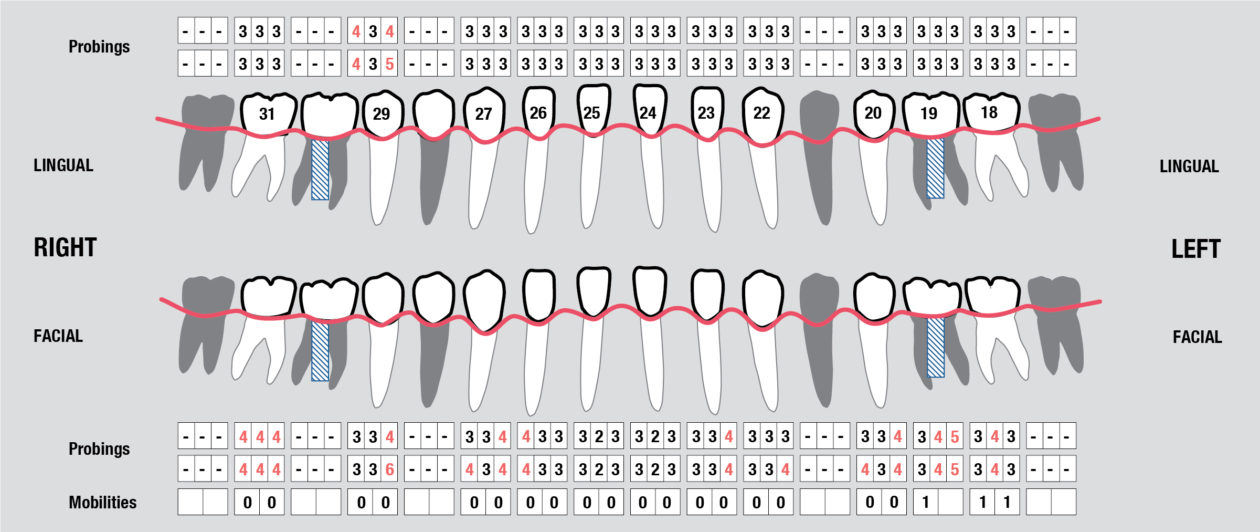

Full Mouth Radiographic Series, Maxillary and Mandibular Intraoral Scans, Digital Jaw Relation Recording with a Leaf Gauge, Complete Photographic Series, Periodontal Charting, Restorative Charting.

Connective tissue grafting was accomplished pre orthodontically to cover the root surfaces in teeth nos. 11 and 12.